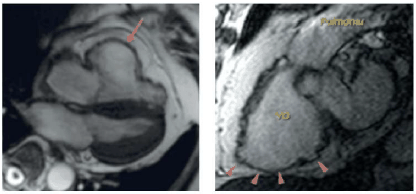

Paciente de 38 anos, natural de Itabuna, sul da Bahia, comparece ao cardiologista para investigação de quadro de insuficiência cardíaca com arritmias ventriculares frequentes, com morfologia tipo BRE. Realizou a ressonância cardíaca reproduzida abaixo.

Para esse caso, a hipótese diagnóstica mais provável é